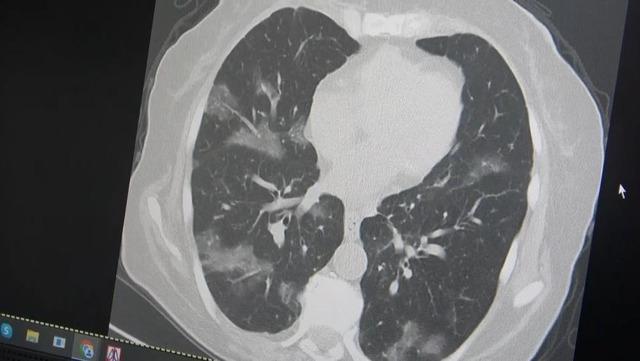

Kanserli bir hastanın akciğerlerinden örnek veren Özkaya, şöyle konuştu: “60 yaş üstü olması ve kemoterapi görmesi nedeniyle virüsün akciğerlere rahatlıkla indiğini görüyoruz. Bu yaza damgasını vuracak yeni virüsün bu olduğunu düşünüyoruz” dedi.